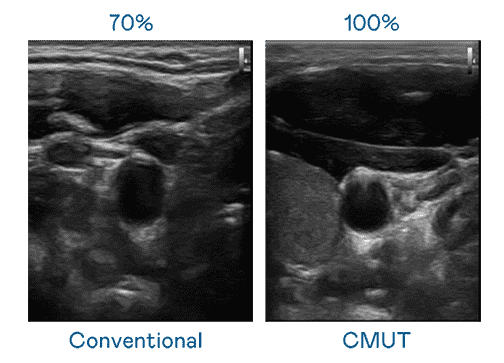

CMUT 技术是一种用电容式微机电元件来产生超音波讯号的技术。。与传统 PZT 压电式技术相比,,,CMUT 频宽增加 30%,,,,更宽频的超音波讯号让影像解析度大幅提升,,,是实现高影像品质医疗超音波扫描、、、促进精准医疗发展的关键技术。。。。

大频宽带来超清晰影像

超音波影像的解析度高低,,,首先取决于探头能发出的讯号频宽。。。。尊龙集团 CMUT 可提供高清晰的超音波讯号,,,提供高频宽、、、、高灵敏度、、、、影像纹理细节更高的超音波影像,,,,协助医护人员缩短影像判读时间及利用精准的医疗影像进行诊断。。。